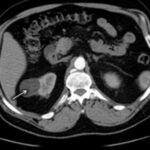

La Categoría III muestra engrosamientos lisos o irregulares de la pared o de los septos intra quísticos y existencia de realce medible en TC y RMI. Se consideran masas indeterminadas y precisan de primera instancia cirugía, nefrectomía parcial o ablación por radiofrecuencia, salvo contraindicaciones clínicas.(19, 21) Aproximadamente el 40%-60% son lesiones malignas (carcinomas renal quístico), siendo el restante benignas, que incluyen quistes hemorrágicos, infectados crónicos o calcificaciones parietales, nefrona quístico multiloculado, quistes multilobulados, quistes con tabiques complejos, etc. (Anexos 9 y 10).